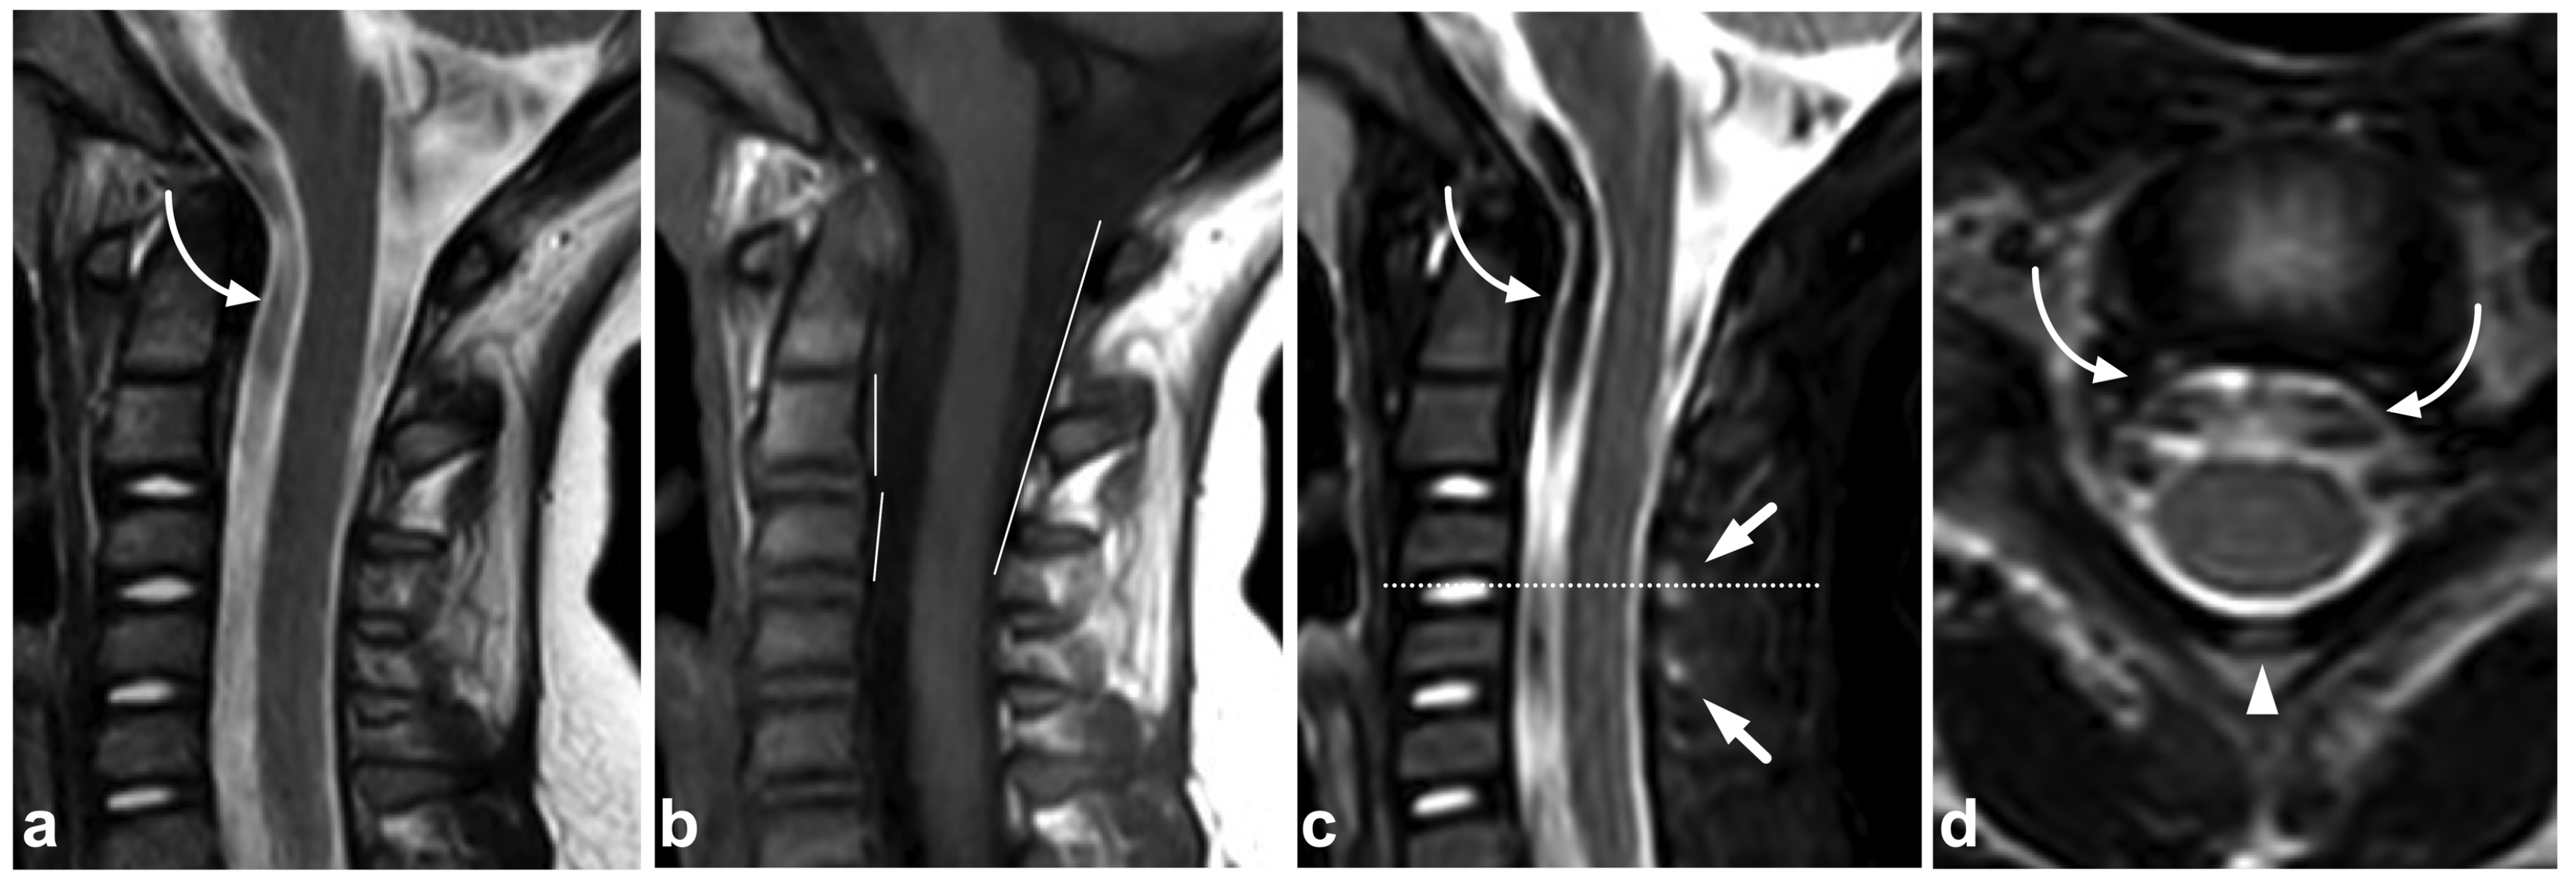

Figure 1.

(a) Sagittal T2-weighted. (b) Sagittal T1-weighted. (c) Sagittal STIR. A 9-year-old female, emergency MRI after a horseback riding accident. MRI demonstrates traumatic changes in vertebral bodies Th3–Th9, of which Th5, Th7, and Th8 have structural compressions (arrows). Th3, Th4, Th6, and Th9 have contusions without visible height loss (arrowheads).

Figure 2.

(a) Sagittal T2-weighted. (b) Sagittal T1-weighted. (c) Sagittal STIR. (d) Axial T2-weighted. A 16-year-old female, back pain after falling down the stairs. Burst fracture in L2 (arrow) with a fragment protruding into the spinal canal and compressing the conus medullaris. Edema can be seen in the conus medullaris immediately above the most compressed level (small arrow). In L4, there is a stable compression fracture (arrowheads). No intraspinal hematoma can be seen. Minor paraspinal edema/hematoma is best demonstrated in the axial image (d).